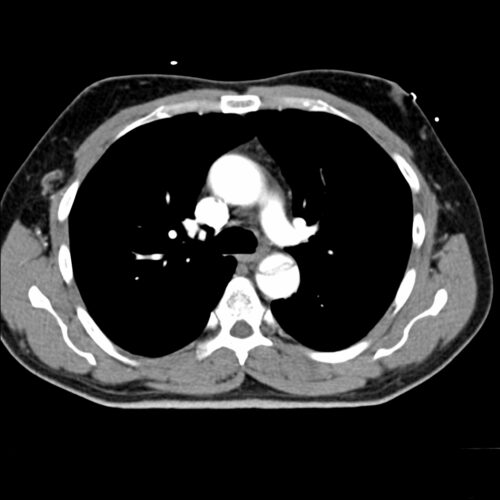

Als Dissektion bezeichnet man einen inneren Einriss der Aortenwand, den sogenannten „intimomedialen Einriss“ mit Aufspaltung der Tunica media und Ausbildung eines falschen Lumens, welches sich, bedingt durch den pulsatilen Blutstrom, nach antegrad oder retrograd ausbreiten kann. Der primäre Einriss wird als „entry“, mögliche Wiederanschlüsse des falschen Lumens an das Originallumen des Gefäßes als „reentry/ies“ bezeichnet.

Nach der Erhebung des Pulsstatus als obligater Basisdiagnostik kommt der notfallmäßig durchgeführten CT-Angiographie von supraaortalen Gefäßen, thorakaler und abdomineller Aorta die diagnostisch entscheidende Rolle zu.